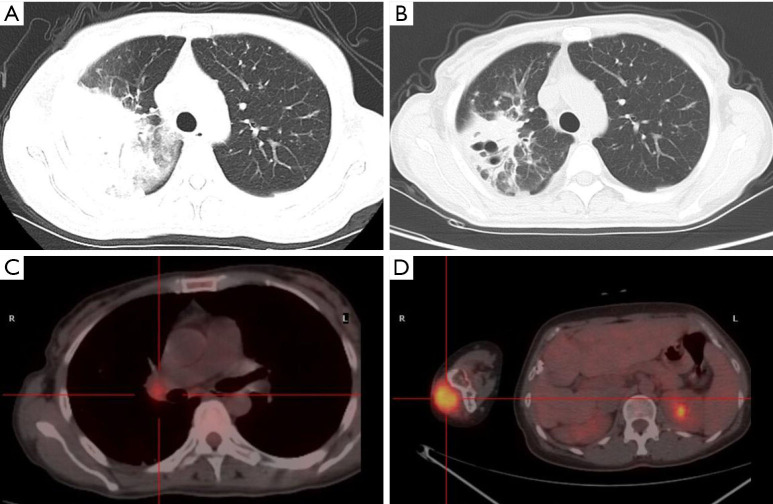

Background: Pulmonary epithelioid hemangioendothelioma (P-EHE) is a rare vascular tumor derived from mesenchymal cells with an incidence of about 1/1 million. The etiology remains unclear, and there are no established treatment guidelines. The tumor can occur in a variety of organs, among which the liver, lung and bone are the most commonly involved, with different clinical manifestations, mainly depending on the organ involved, but none of them is specific. Most epithelioid hemangioendotheliomas are indolent and can achieve long-term survival even without any treatment. The prognosis of patients with primary liver or lung diseases is poor, and P-EHE has the highest mortality rate. Clinical reports of airway stenosis caused by P-EHE are exceedingly rare.

Case description: We report a case of a middle-aged female patient with initial diagnostic difficulties leading to misdiagnosis, which was eventually confirmed as P-EHE by pathology. Despite radiotherapy, chemotherapy, and antiangiogenic therapy, the efficacy was limited, resulting in severe airway stenosis in the advanced stage of the disease, with severe clinical symptoms. After bronchoscopic cryoablation, the oxygenation index of the patient was significantly improved, and the quality of life was significantly improved.

Conclusions: This case underscores the complexity of diagnosing and managing P-EHE and illustrates the potential of cryoablation as an effective treatment for severe airway stenosis secondary to this rare tumor.